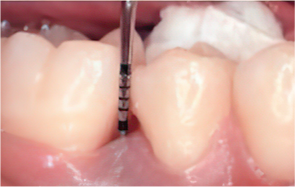

엠도게인 수술과정

-

STEP 01

잇몸을 절개

STEP 02

Scaling Root Planning을 실시